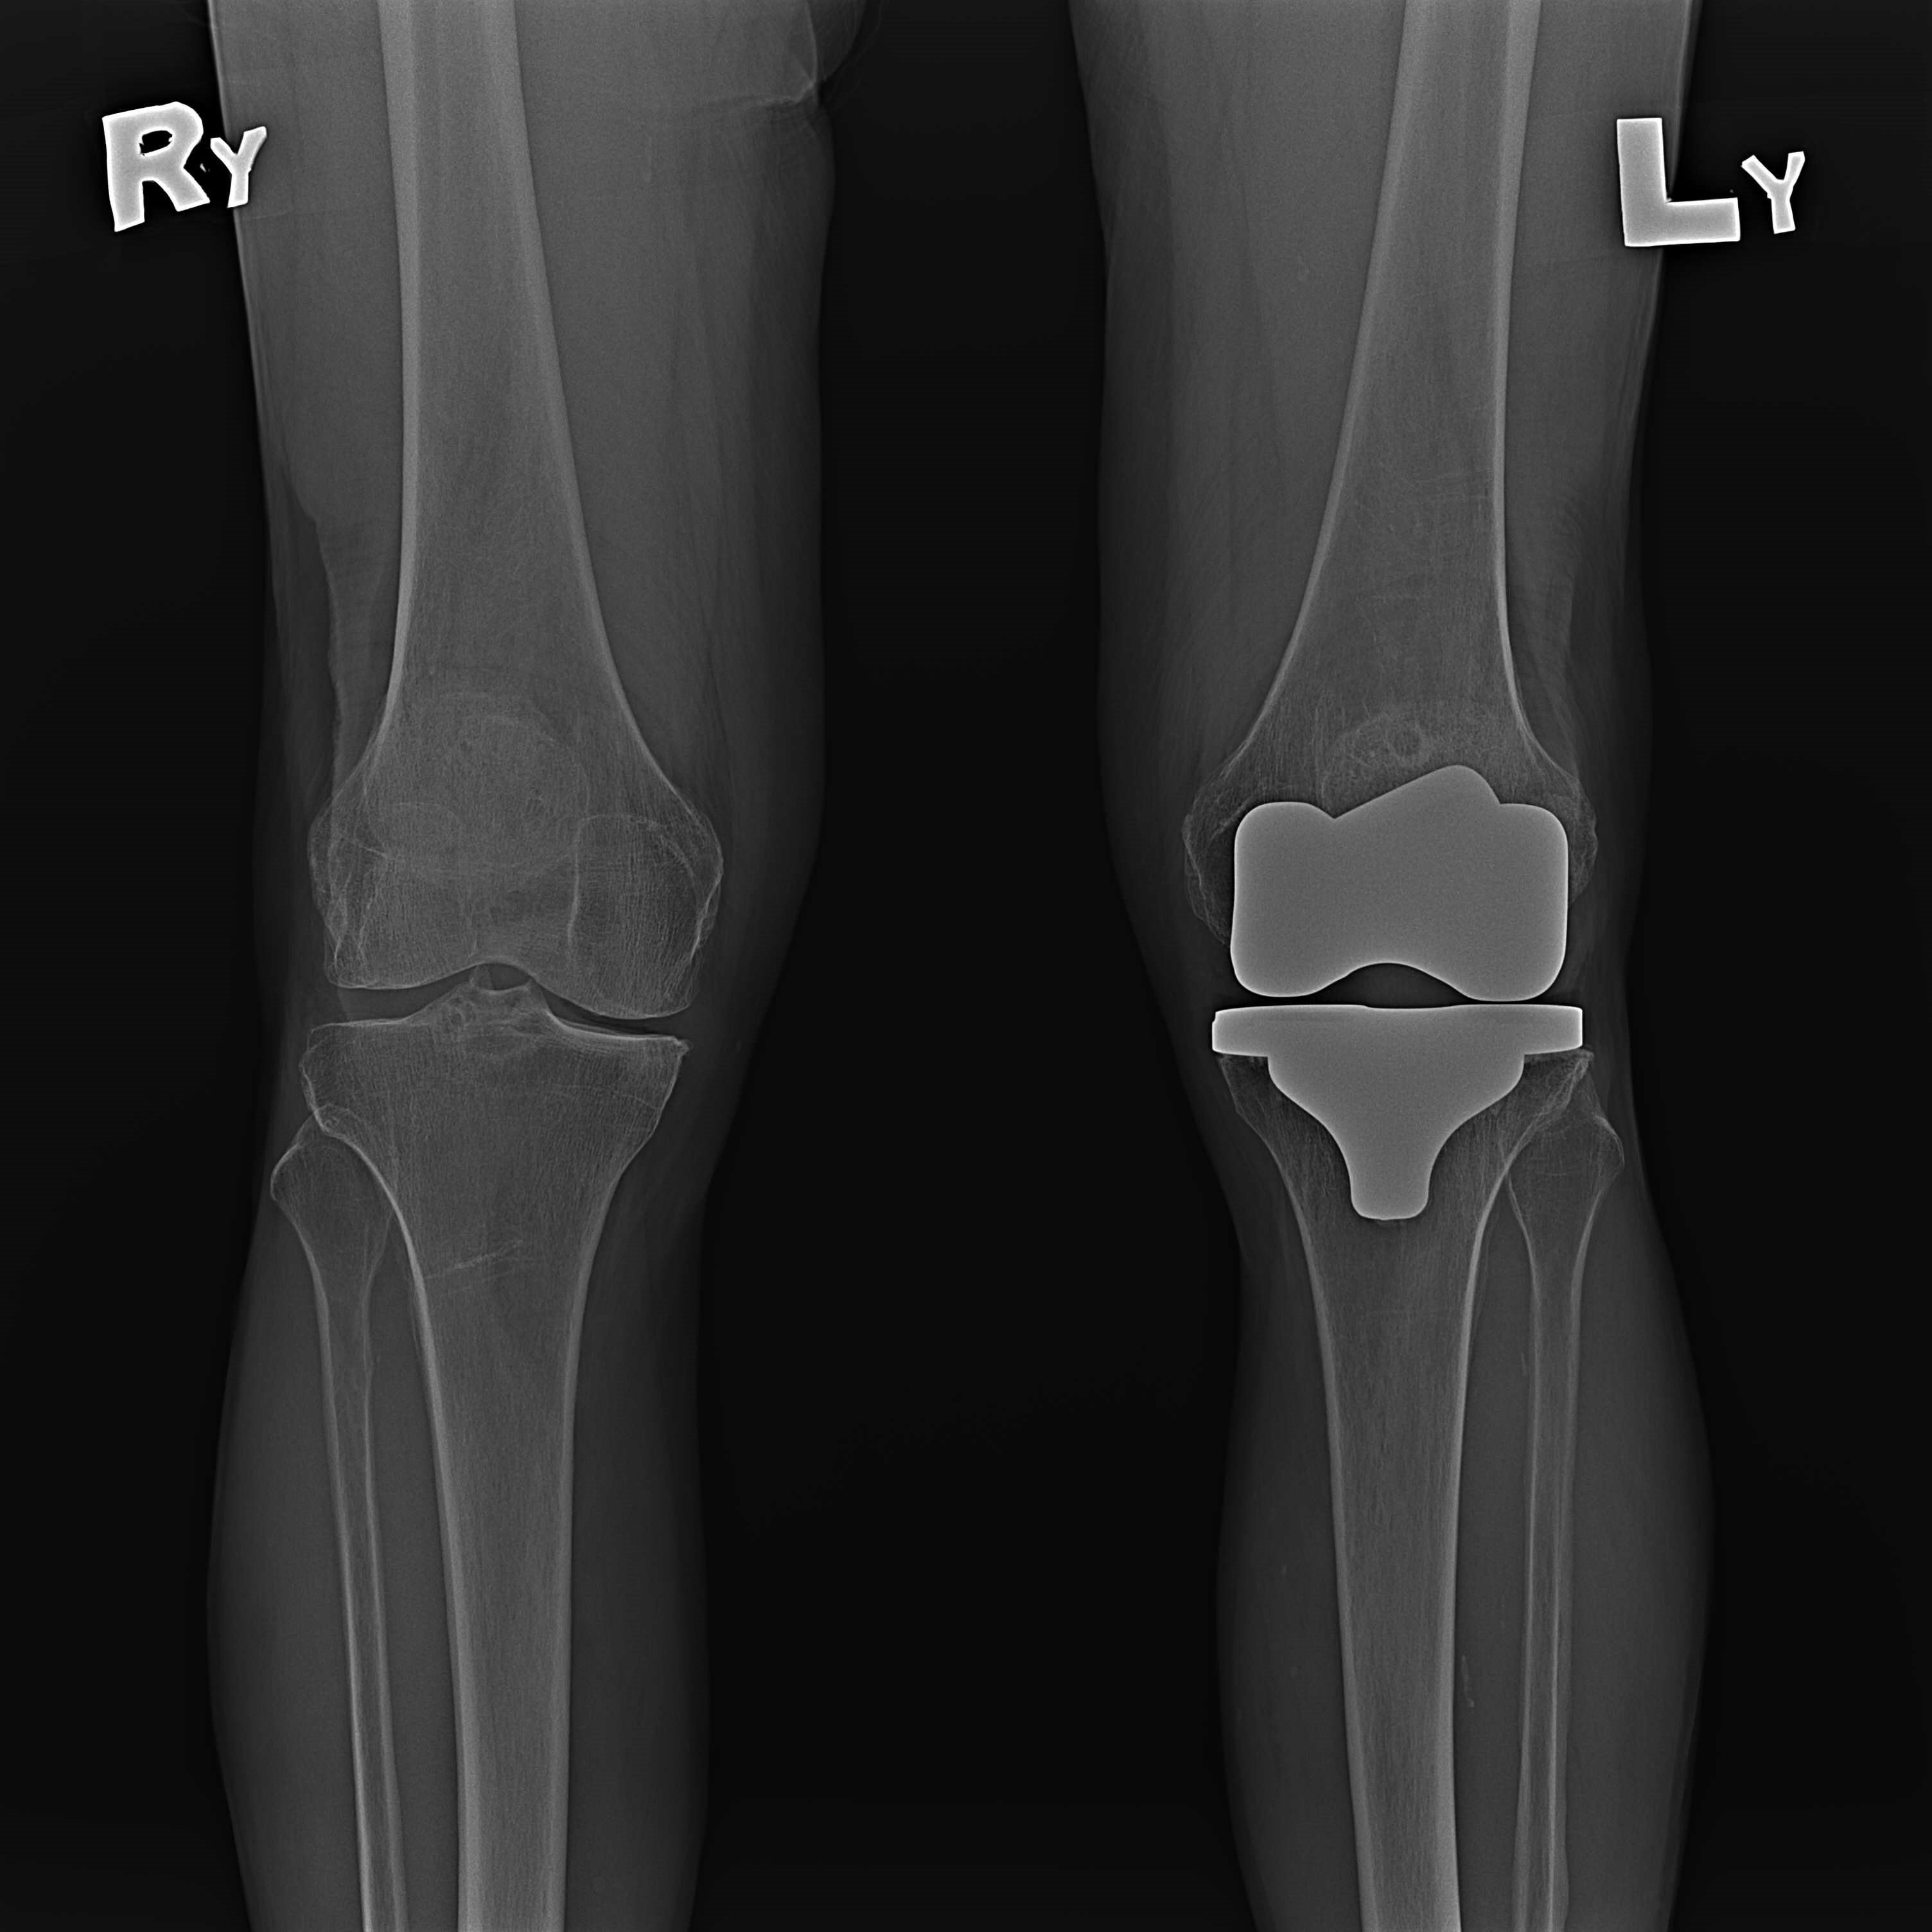

機器手臂手術 首頁 案例分享 膝關節手術 機器手臂手術 蔡女士 78歲 術前 術後 陳女士 70歲 術前 術後 術前 術後 ANGEVINE女士 73歲 術前 術後 U.S.A Mark 73歲 術前 術後 藍女士 78歲 術前 術後